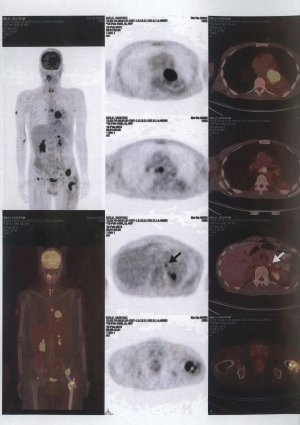

Resim 30

PET-CT ise günümüzde kullanımı artan, çok gelişmiş bir görüntüleme metodudur. Vücutta nerelerde kitle olduğu ve bunların iyi yada kötü mü oldukları hakkında fikir verir (resim-30).